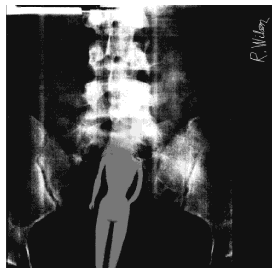

• Barbie (bogus)